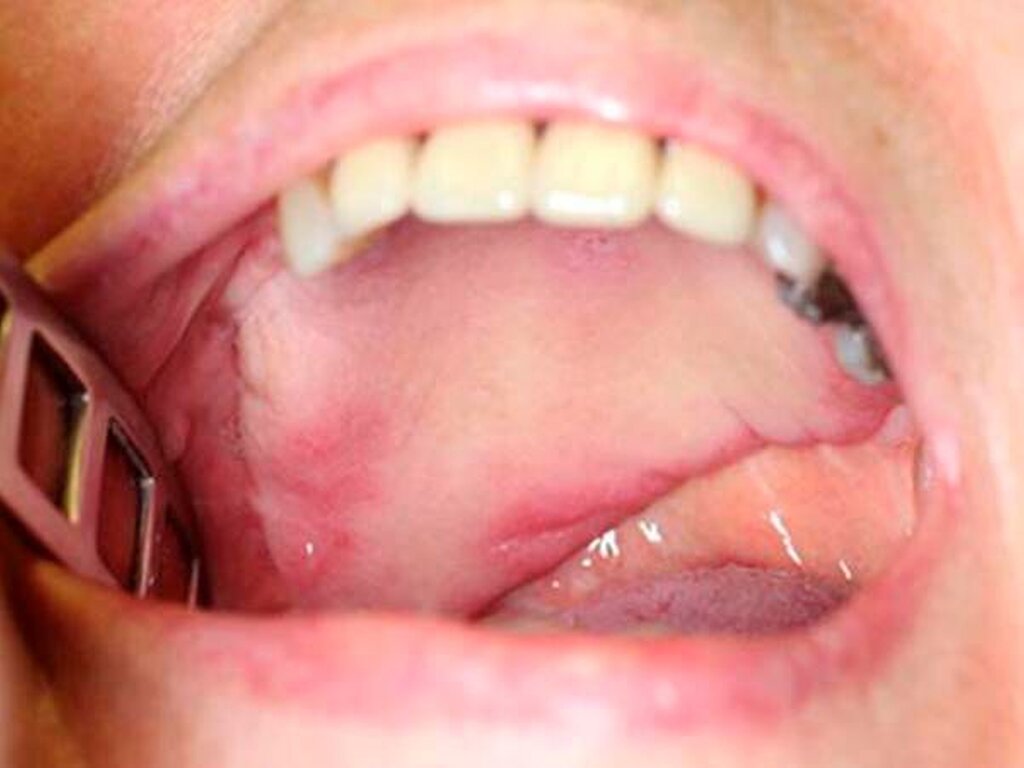

Die Frau stellte sich mit einer großen intraoralen harten, nicht ulcerierenden Vorwölbung des Gaumendachs vor. Sie gab an, bereits vor circa 30 Jahren sei die Diagnose eines kleinen, gutartigen Speicheldrüsentumors im Bereich des harten Gaumens durch eine Gewebeprobe gestellt worden. Damals hatte sie jegliche Therapieoptionen verweigert und auf ein abwartendes Verhalten bestanden.

Mittlerweile war der Tumor verdrängend nach kranial bis in die Nasenhaupthöhle und nach kaudal in die Mundhöhle teilweise bis auf das Niveau der Okklussionsebene gewachsen. Der extraorale Befund war gänzlich unauffällig.